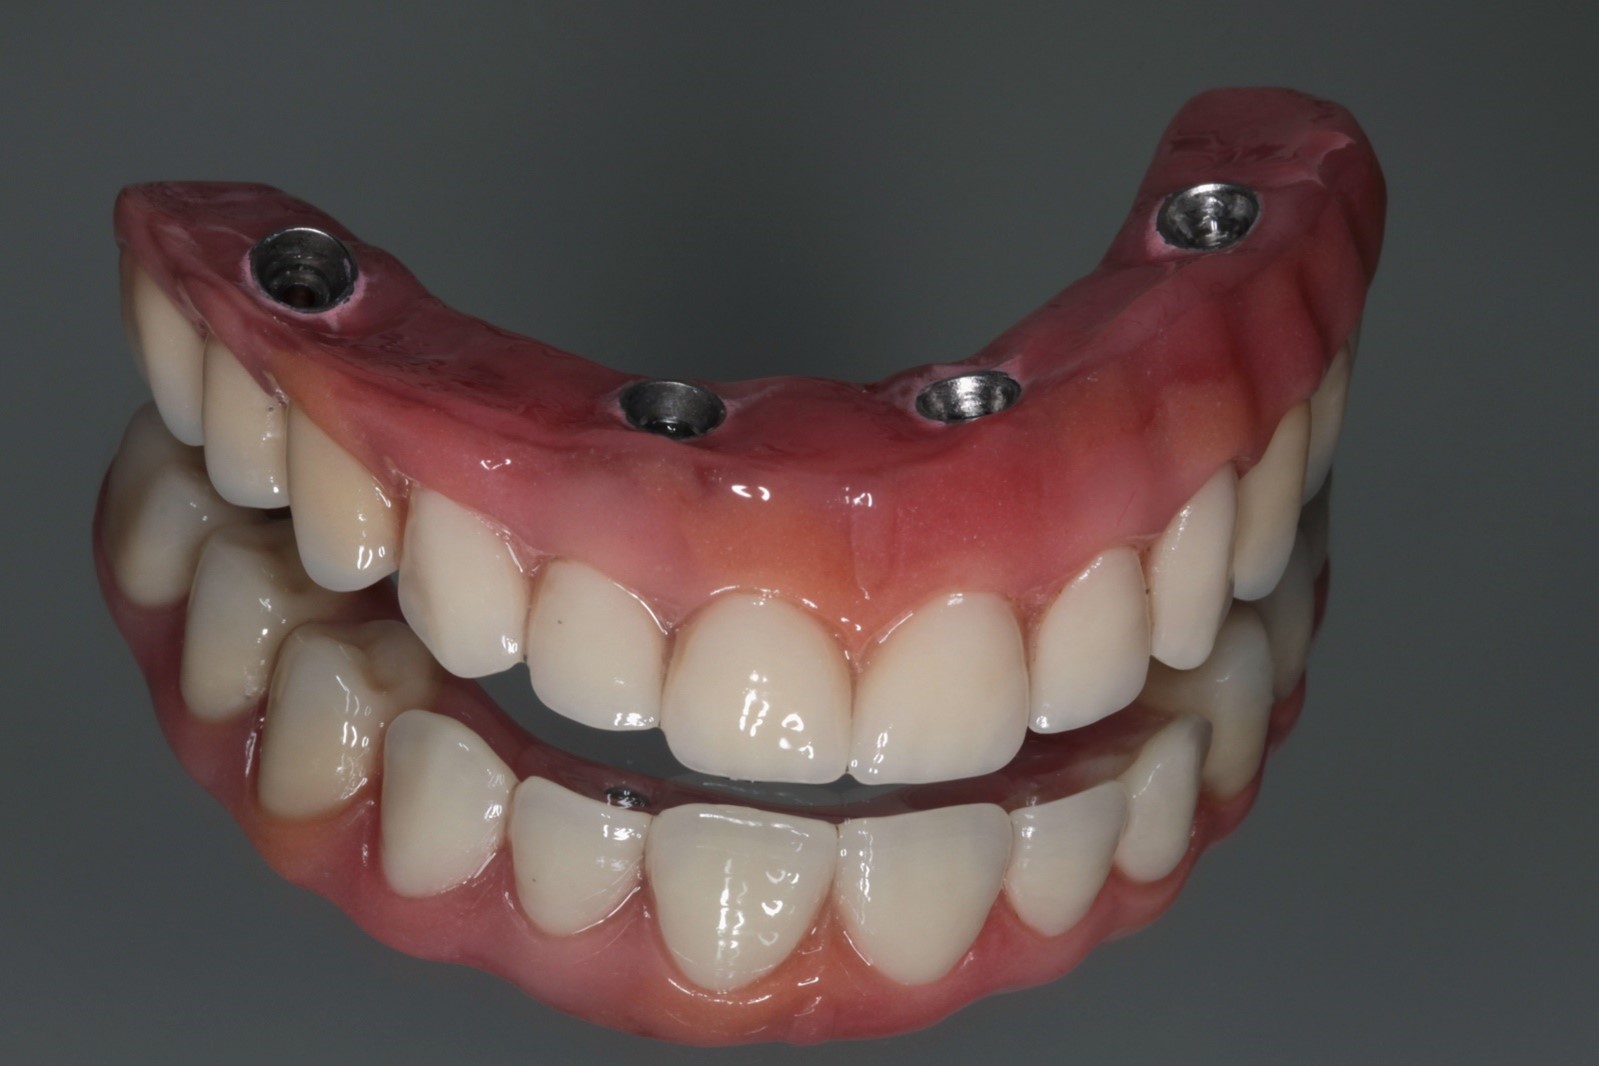

Todos os implantes atingiram um torque de 80 N, possibilitando a realização de carga imediata. Mini pilares retos com transmucoso de 2mm foram instalados nos implantes anteriores e mini pilares angulados de 30 graus com transmucoso de 3mm nos distais, corrigindo a ajuste dos implantes e sustentando o assentamento passivo da barra.

A sutura simples dos tecidos foi realizada, seguida pela moldagem de transferência. O plano de cera foi confeccionado, assim como a prova dos dentes em cera, utilizando dentes Vita MFT da Wilcos®. No terceiro dia, a prótese tipo protocolo final foi instalada em carga imediata. O paciente retornou após 10 dias para remoção das suturas. No momento da escrita deste relatório, o caso conta com 26 meses de acompanhamento. Os resultados demonstraram sucesso na osseointegração dos implantes e plena satisfação do paciente, que em três dias já estava reabilitado e utilizando uma prótese fixa sobre implantes, atingindo a expectativa alinhada previamente.

FIG. 10a e b – Instalação da prótese protocolo.